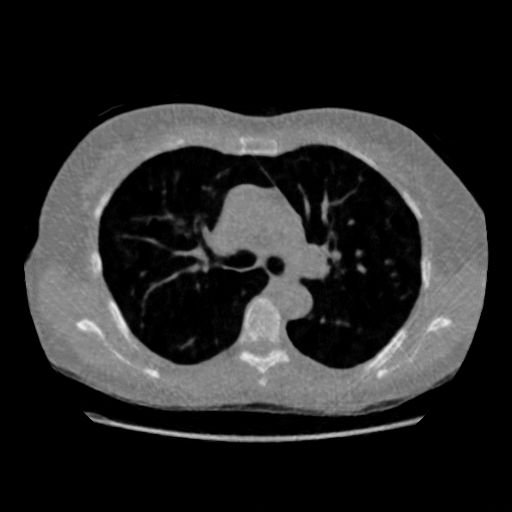

4.3 Few-View CT Reconstruction

In this section, the reconstruction performance of our proposed framework under few-view conditions will be tested. For the parallel-beam and fan-beam geometry, the number of views increases from to , uniformly distributing from to and to respectively. Such settings provide a complete benchmark of reconstruction performance, ranging from extremely sparse to relatively complete, full-view CT reconstruction. The experiment results are shown in Fig.5. Additionally, the ground truth, few-view ( views), and full-view ( views) CT reconstruction results of different methods are shown in the first and third rows of Fig.7 (parallel-beam, LIDC-IDRI dataset), and Fig.8 (fan-beam, LIDC-IDRI dataset).

(a) Ground Truth

43.87dB

(b) ASD-POCS

47.96dB

(c) RBP-DIP

34.46dB

(d) DIP

26.63dB

(e) MED50

29.03dB

(f) RED-CNN